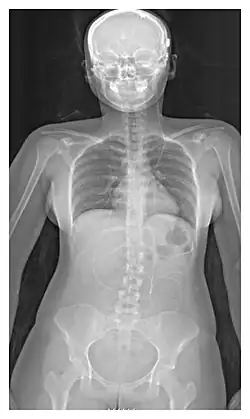

L'emplacement de la dérivation est déterminé par le neurochirurgien en fonction du type et de l'emplacement du blocage provoquant l'hydrocéphalie. Tous les ventricules cérébraux sont candidats à la dérivation. Le cathéter est le plus souvent placé dans l'abdomen, mais d'autres emplacements incluent le cœur et les poumons. les dérivations peuvent souvent porter le nom de la voie utilisée par le neurochirurgien. L'extrémité distale du cathéter peut être située dans à peu près n'importe quel tissu comportant suffisamment de cellules épithéliales pour absorber le LCR entrant. Ci-dessous quelques plans de routage courants pour les dérivations cérébrales :

| Dérivation ventriculo-péritonéal (Dérivation VP) | Cavité péritonéale |

| Dérivation ventriculo-pleural (Dérivation VPL) | Cavité pleurale |

| Dérivation lombaire-péritonéal (Dérivation LP) | Cavité péritonéale |